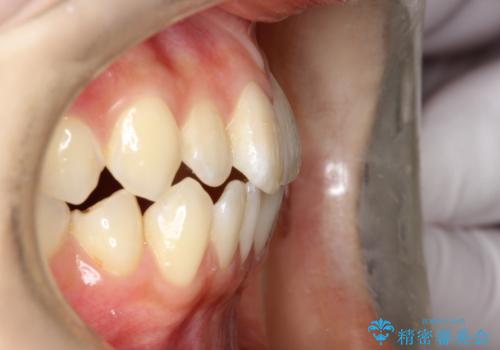

前歯のガタつき、下顎の前突感を治したい インビザライン矯正例

- 学生時代に矯正治療を経験されていましたが、その後の後戻りによる前歯の叢生・下顎の前突感を主訴に来院されました。叢生や口元の突出感が軽度であった為、非抜歯にて側方拡大やIPRを組み込んでインビザラインにて治療を計画しました。前歯部にクロスバイトがあり、治療途中に上顎前歯が下顎前歯を乗り越えなければならない時期もありましたが、患者様の協力的なマウスピース装着もあり、良好な配列を達成しました。上下左右の親知らずは、当院にて矯正開始前に抜歯しました。